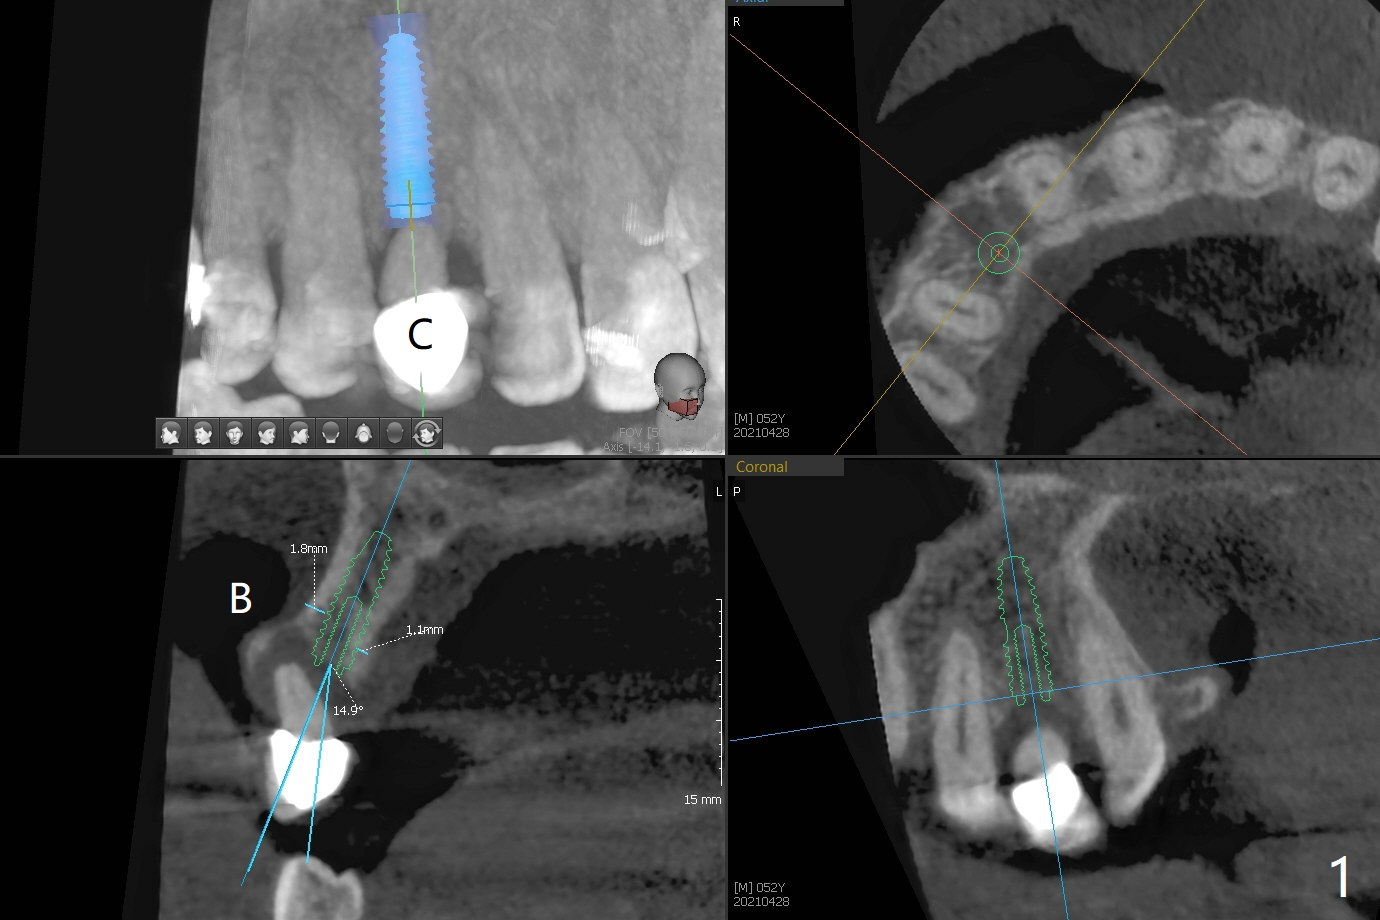

A 52-year-old man requests extraction of the mobile deciduous canine for implant (Fig.1). Use sticky bone (Fig.2 red) to maintain the canine prominence (>). In fact, there is apical perforation of the deciduous canine (Fig.3-5: *). Before bone graft, place a small piece of PRF for repair. The patient refuses to close the diastema between #8 and 9 (Fig.4 ^). Since the cancellous bone is 2.9 mm (Fig.3), it is safe to place a narrow implant (Fig.7). Return to Protect Graft Clindamycin 手术 15 Xin Wei, DDS, PhD, MS 1st edition 04/28/2021, last revision 05/27/2021